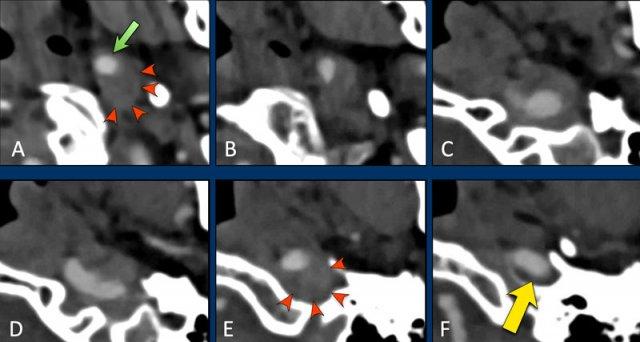

Bóc tách dừng lại tại nền sọ

Bệnh nhân này có bóc tách động mạch cảnh.

Trong hình A, chúng ta thấy lòng mạch bị chèn ép ở vị trí lệch tâm (mũi tên xanh lá).

Đường kính ICA bị giãn rộng bởi khối máu tụ trong thành mạch (đầu mũi tên đỏ).

Khi theo dõi ICA lên phía trên, tổn thương bóc tách tiếp tục đến hình E (đầu mũi tên).

Tại mức nền sọ, nơi ICA đi vào ống cảnh (đoạn đá thẳng đứng), tổn thương bóc tách dừng lại và ICA có hình ảnh bình thường (mũi tên vàng).